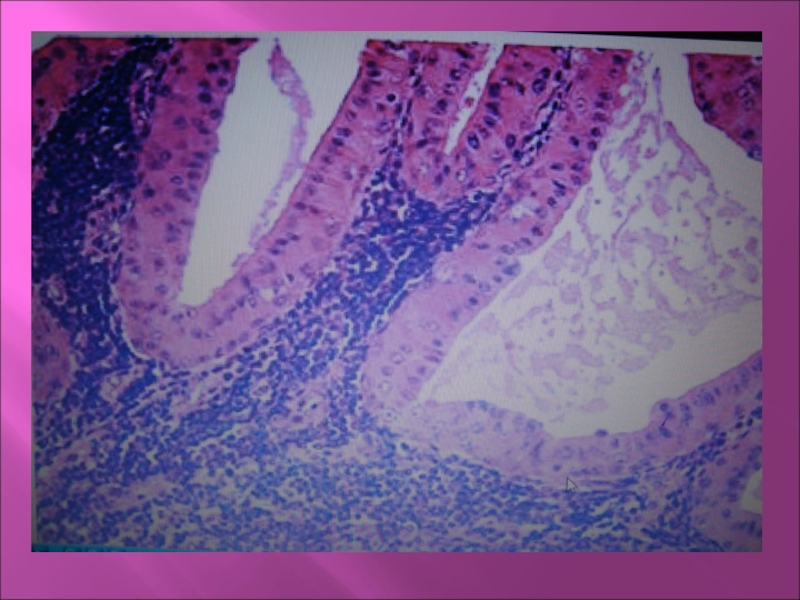

Микроскопически: Призматический эпителий

с резко эозинофильной цитоплазмой располагается в два ряда, формирует сосочковые выросты. Строма инфильтрирована лимфоцитами.